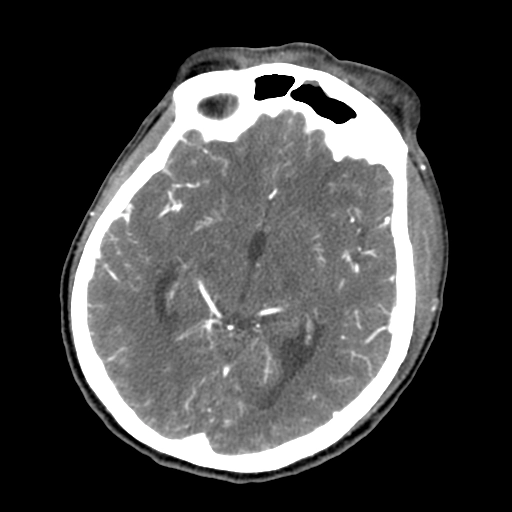

• Huyết khối xoang hang (Cavernous sinus thrombosis - CST

Huyết khối xoang hang (Cavernous sinus thrombosis - CST